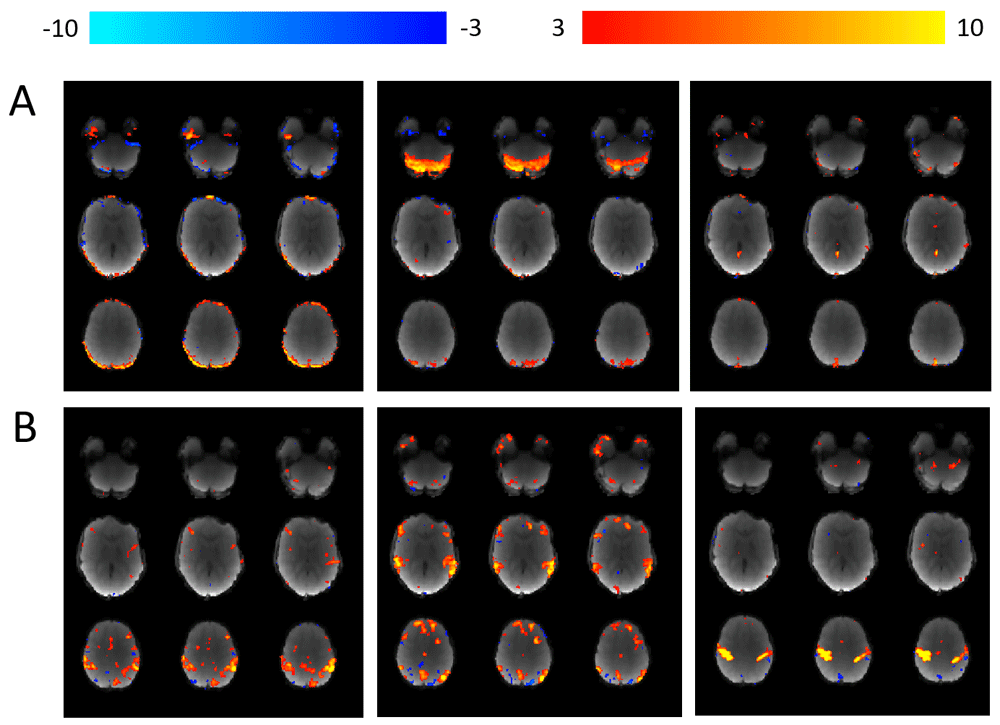

Resting-state functional data. For the functional resting state data, FEAT (Version 6.0062) will be used to run motion correction of the functional data using MCFLIRT63, distortion correction using FUGUE, brain extraction using BET64 and grand mean scaling62. The following images will be prepared for input into FEAT: (1) reference image for motion correction of the functional data and (2) fieldmap and fieldmap magnitude images. A single-band reference (SBref, acquired at the start of the functional scan) will be bias corrected using FAST and then used as an alternative reference image for motion correction. The fieldmap magnitude image will initially have non-brain matter removed using BET and will then be manually edited (see Figure 3). Subsequently, the fsl_prepare_fieldmap function will be used to create a fieldmap image (for an example see Figure 3). FEAT will also register the SBref to the T1 weighted structural image using FMRIB’s linear image registration tool (FLIRT, rigid-body and boundary-based registration)63,65,66. FLIRT and FSL’s non-linear image registration tool (FNIRT) are then used to register each participant’s structural T1 weighted image to a Paediatric Template image54 (see Figure 4 for example of Paediatric Template). MELODIC (model-free fMRI analysis using probabilistic independent component analysis) will decompose functional data into spatially independent components67, which will subsequently automatically be labelled as signal (i.e. not movement) or noise (i.e. motion or physiological artefact) using ICA-AROMA (Automatic Removal of Motion Artifacts68). ICA components that depict physiological noise or movement are automatically removed (see Figure 5 and Figure 6). Lastly the data is high pass temporal filtered at 0.01 Hz (100 s period).

Using MELODIC67, each individual participant’s 4 dimensional fMRI data is decomposed in to independent spatial and temporal components. ICA-AROMA is then used to (i) automatically identify “movement” components and (ii) remove them from the data68. (A) Examples of three separate components labelled as “movement” and subsequently removed from the data. (B) Examples of three separate components that were not labelled as movement and therefore remain within the data.